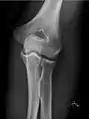

• Knee - AP and Lateral. Intra Condular projections on request

• Patella - Skyline projection